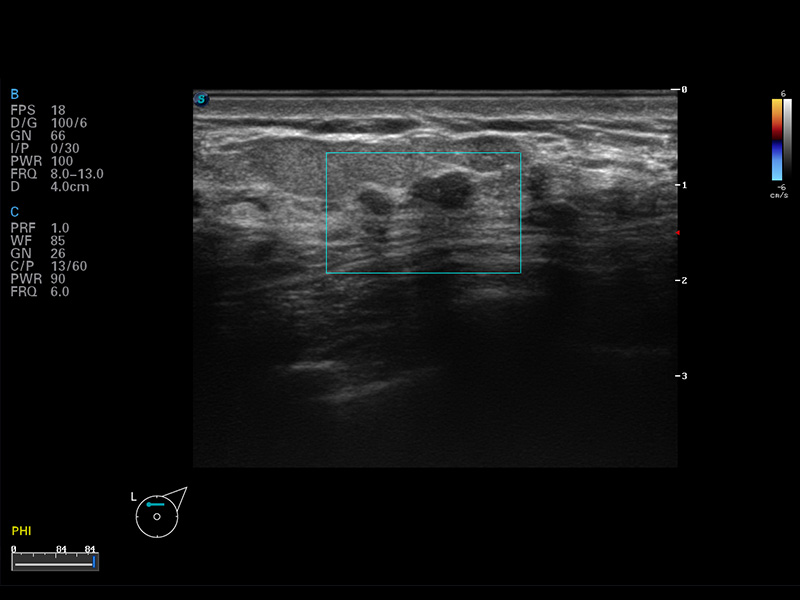

S8 EXP便携式彩色多普勒超声诊断仪是狗万官方网站研发的高端全身应用型便携彩超。高通道的VIS平台融合可视化(Visual)、智能化(Intelligent)和人性化(Smart)的特点,配以狗万官方网站自主研发生产的探头大家族,使您能够快速、准确的获得病人信息,提高工作效率的同时减轻疲劳。

μ-Scan微米成像